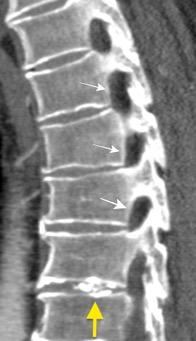

Osteoporosis

Menopausia

Esteroides

Infiltración neoplásica

Mieloma múltiple

Metástasis

1. Osteoporosis en Alzheimer con desnutrición, hipoproteinemia y déficit de B12.

Fracturas dorsales

Wu M.-H., Huang T.-J., Cheng C.-C., Li Y.-Y., Hsu R.W.-W. Role of the supine lateral radiograph of the spine in vertebroplasty for osteoporotic vertebral compression fracture: A prospective study. BMC Musculoskelet. Disord. 2010;